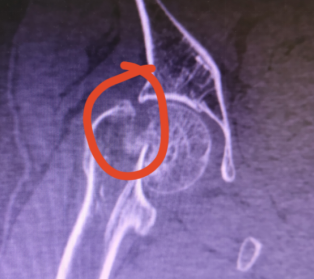

关节外科和创伤骨科收治较多的是股骨颈骨折的患者。股骨颈骨折是髋部较常见的损伤,是指由股骨头下至股骨颈基底部之间的骨折,是一种在老年人群中非常常见的骨折,骨折术后不愈合率及股骨头坏死发生率极高。

股骨颈骨折多数因行走跌伤时下肢扭转、内翻或外翻造成,受伤时多臀部着地,伤后髋部疼痛,不能站立和行走。路滑、路不平及上下台阶是骨折的诱发因素,骨质疏松是骨折的内在因素。股骨颈骨折大多数有比较明显的移位,骨折不稳定,因此需要住院手术治疗。